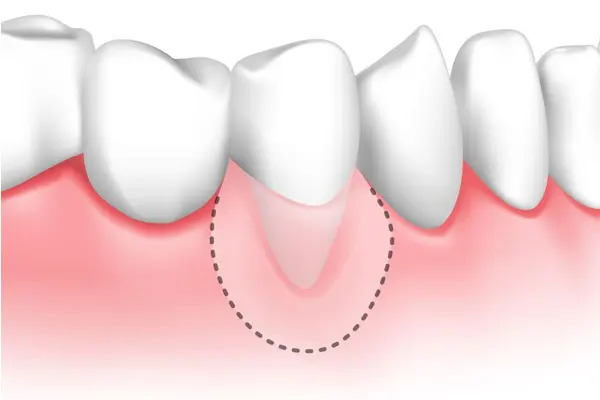

اکسپوز ریشه دندان به وضعیتی گفته میشود که در آن بخشی از ریشه دندان که معمولاً توسط لثهها پوشانده شده است، در معرض دید قرار میگیرد. ریشه دندان معمولاً در استخوان فک و لثهها قرار دارد و از طریق این بافتها محافظت میشود. اما در شرایط خاص، ممکن است لثهها تحلیل بروند یا آسیب ببینند، که باعث نمایان شدن ریشه دندان میشود.